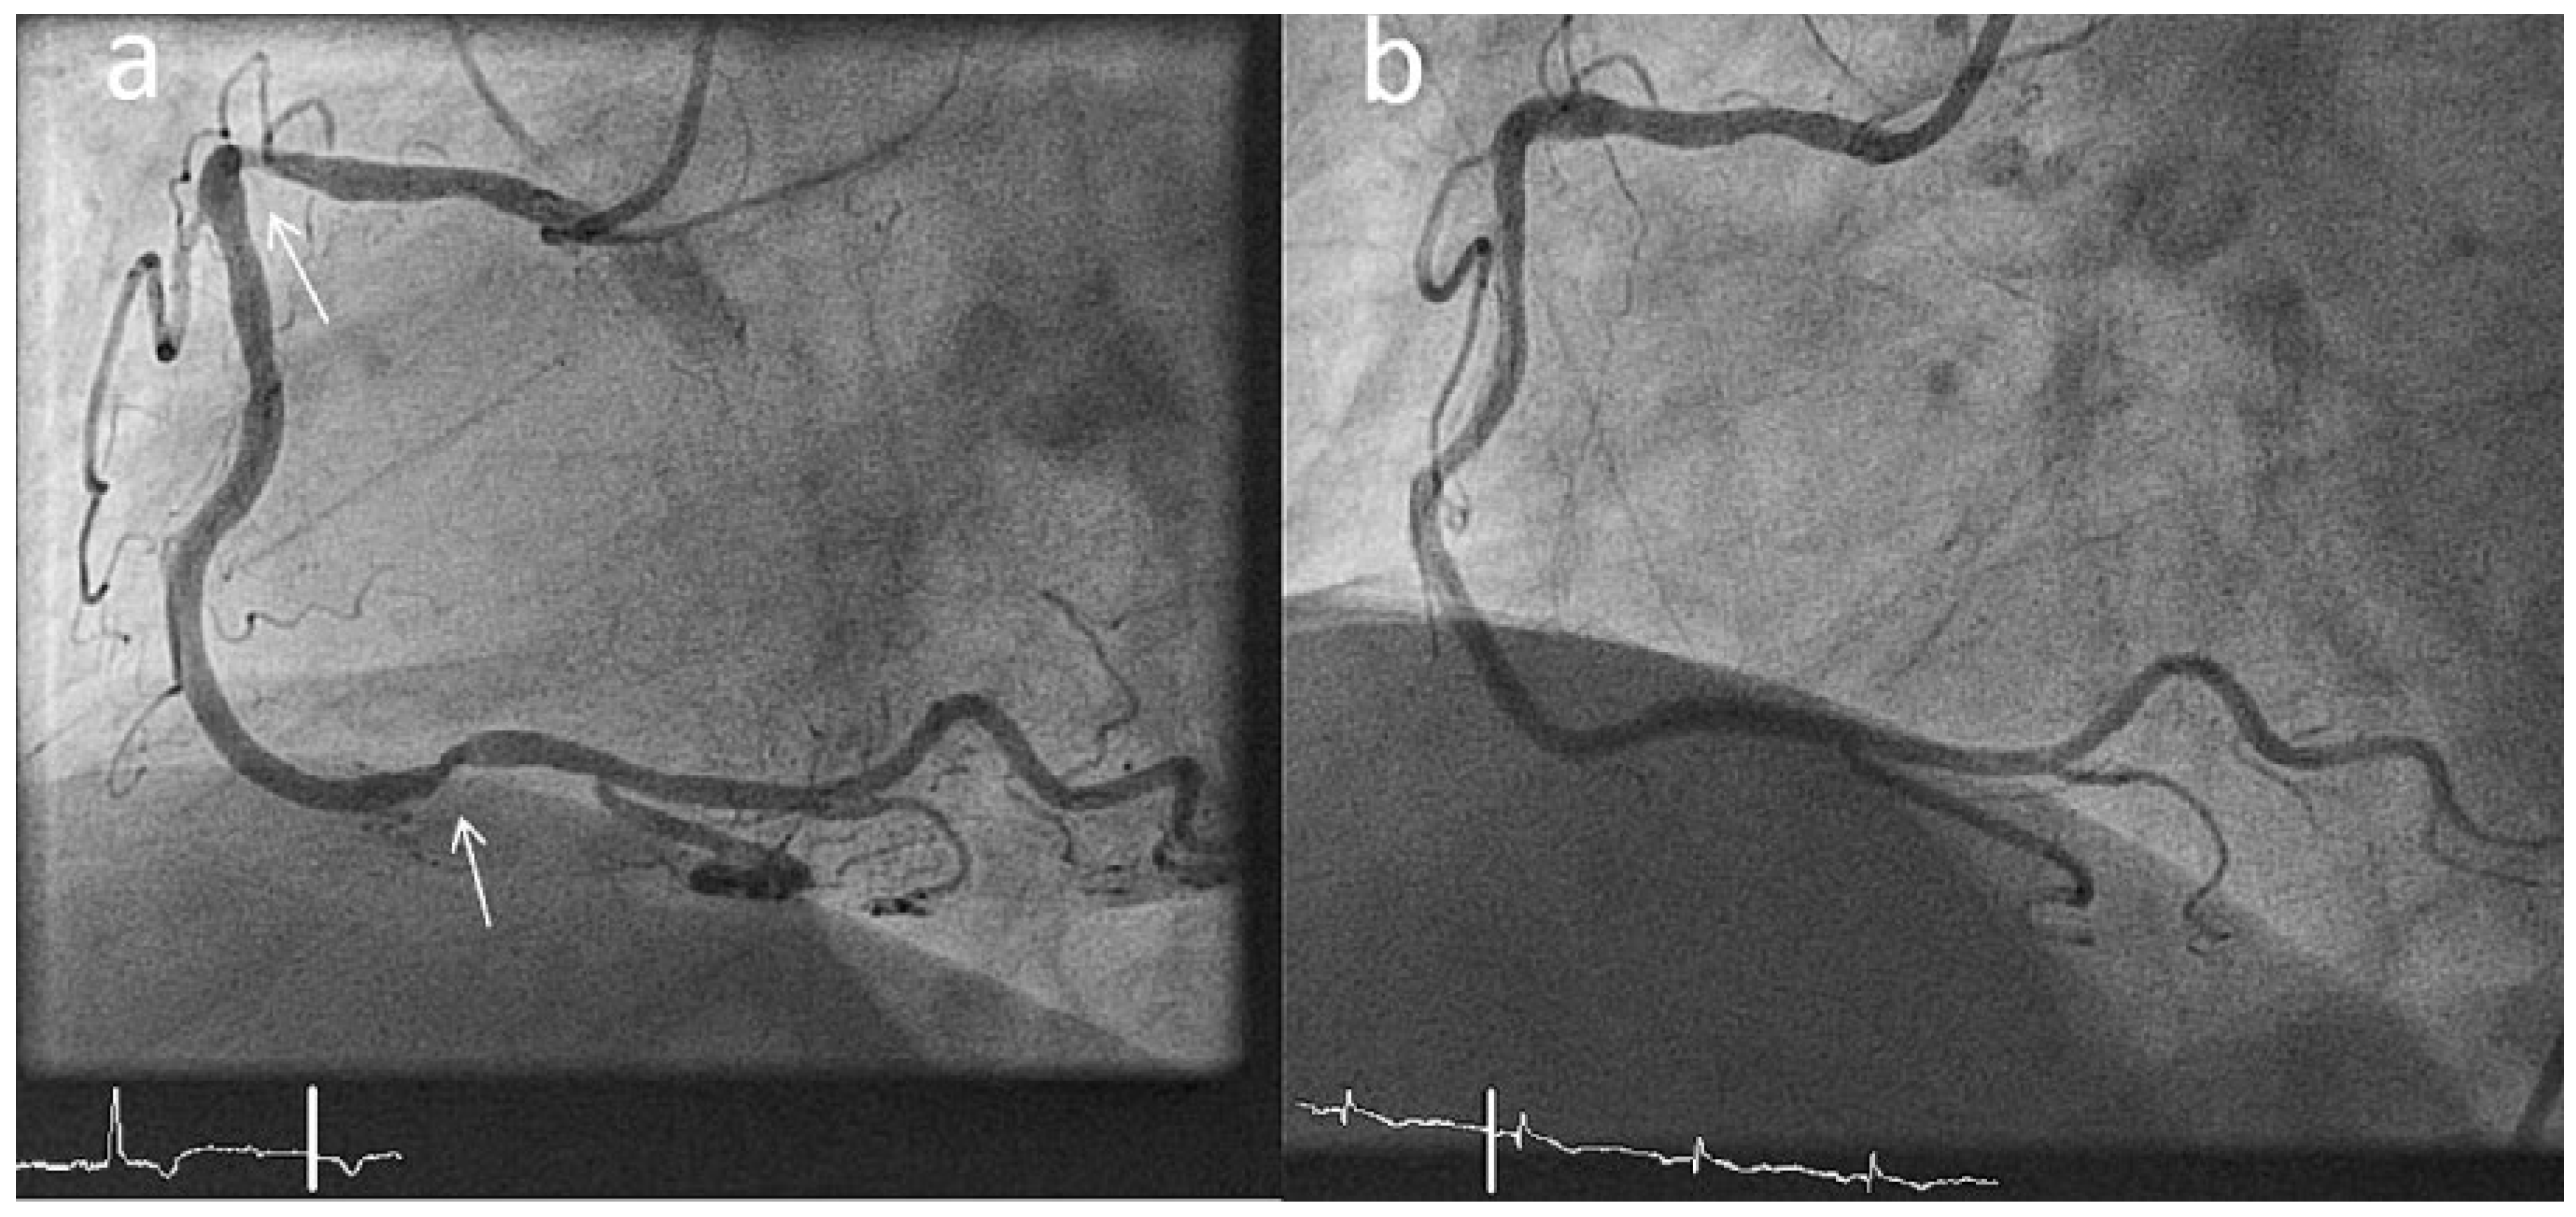

Incomplete Stent Apposition Resolves One Year After Implantation

Case report